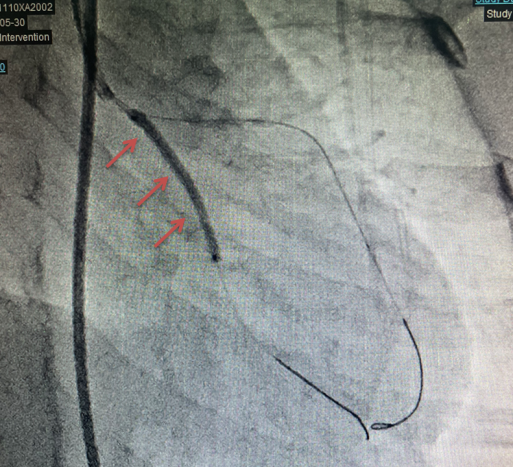

6岁的涵涵(化名)来自东北,聪明乖巧,不幸的是生后4个月她患了川崎病,而且遗留严重的冠状动脉病变。涵涵的妈妈自己是一名医务工作者,深知冠状动脉病变的危险性,非常用心地坚持抗凝治疗。但当地最近的CT冠状动脉造影检查显示左前降支明显钙化、回旋支纤细,而且涵涵出现了明显胸闷胸痛的情况。经当地医生推荐,涵涵和家人来到我们医院。入院后经过详尽的冠状动脉影像和心肌缺血的评估,涵涵的左冠状动脉回旋支起始端长段完全闭塞(图1),而且同位素负荷心肌灌注显像显示心肌侧壁、下壁、前壁多处可逆性缺血,侧枝血管不足以满足心肌的供血。我院心内科刘芳主任团队与中山医院心内科马剑英教授充分讨论后,决定为涵涵进行经导管回旋支再通血运重建手术。

图1. 箭头所示左冠状动脉回旋支(CX)近端长段闭塞,长度17mm,

左前降支(LAD)形成的侧枝供应CX远段